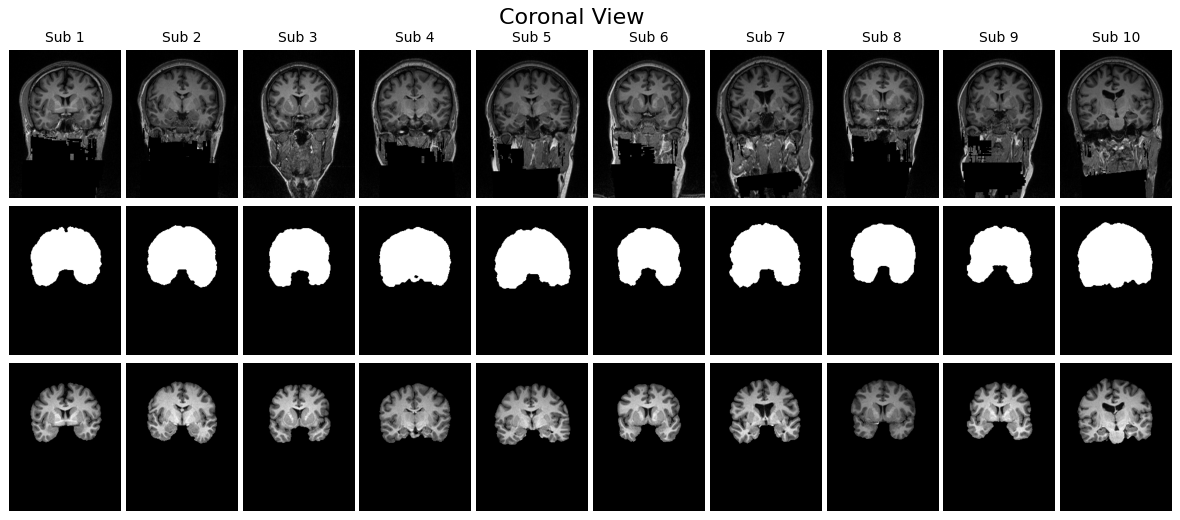

MRI データを読み込んだら、まず「本当に正しく読み込めているか」を確かめることが最初に行うべき作業です。医用画像は三次元のボリュームデータであり、単に配列の shape(形状)を確認するだけでは、脳の構造がきちんと反映されているのか、マスクが対応しているのかを判断することはできません。そのため、可視化による目視確認が欠かせません。

確認方法としては、Z 軸方向の中央スライスを取り出すのがわかりやすいアプローチです。MRI は縦・横・奥行きの三方向にスライスが存在しますが、その中央部分を選ぶことで代表的な断面を観察できます。このスライスを用い、以下の三種類を並べて可視化すると、入力とラベルの関係が直感的に理解しやすくなります。ひとつ目は元の T1 強調 MRI 画像で、脳だけでなく頭蓋骨を含んだオリジナルの状態です。ふたつ目は、その MRI にマスクを適用し脳組織のみを抽出した画像です。三つ目がマスク画像そのもので、白が脳、黒が非脳組織を示すラベル画像です。

さらに、こうした可視化を一人分だけでなく複数の患者について横並びに表示すると、データのばらつきやマスクの位置のずれがないかを効率的にチェックできます。axial(軸位)、sagittal(矢状)、coronal(冠状)の 3 断面で表示することで、読み込んだ配列に異常がないか、ファイルが壊れていないかを一目で確認できます。

こうした目視確認は「前処理や学習を進めてよいかどうか」を判断する品質チェックでもあります。この段階でマスクがオリジナル画像とうまく重なっていなければ、その後どれだけ高度なモデルを学習させても正しい結果は得られません。

visualize_slices_horizontal(voxels, labels, view='axial', n_patients=10)

visualize_slices_horizontal(voxels, labels, view='sagittal', n_patients=10)

visualize_slices_horizontal(voxels, labels, view='coronal', n_patients=10)